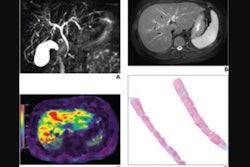

Imaging findings on MRI can help clinicians understand a tumor's "biological behavior" and thus improve their ability to make an accurate prognosis regarding disease recurrence, the group explained: Features such as ill-defined tumor margins, an absence of a tumor capsule, and enhancement of the area around the tumor the arterial phase may indicate that the cancer is aggressive.

Zhang and colleagues sought to assess any connections between MRI exam features and cancer outcomes after microwave ablation in patients with hepatocellular carcinoma, and to develop a post-ablation treatment algorithm based on multiparametric MRI data.

"Diffusion-weighted imaging is an important MRI functional imaging tool with the unique ability to display microscopic functional information such as the tissue cell structure and cell membrane integrity, and its quantitative parameters can provide information on the status of a lesion after treatment," the authors noted.